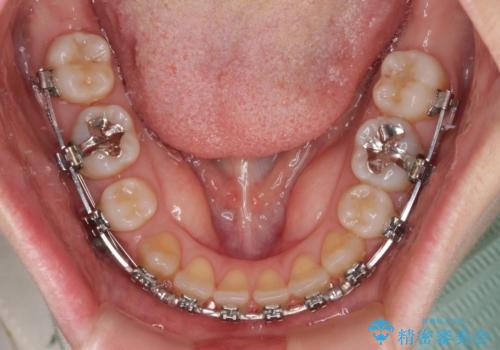

- 矯正装置

- メタルブラケット

マウスピース矯正を検討されていましたが、後戻りの隙間が非常に大きく、奥歯を前方に移動させる必要があるため、ワイヤー装置にて矯正治療を行うこととしました。

舌の突出癖が非常に強く、その影響で隙間ができてしまったので、舌のトレーニングをしっかりと行っていただきました。